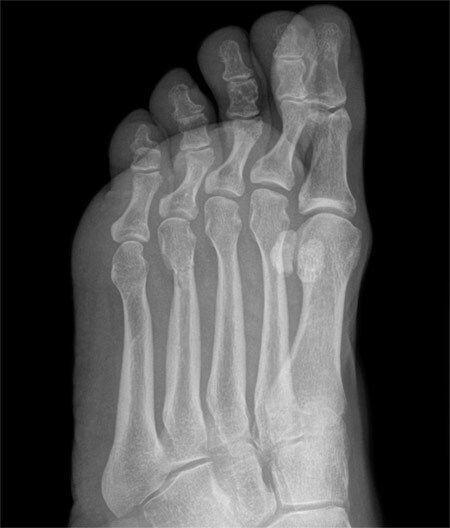

X-RAY QUIZ: Which finding is present on this image?

Start Quiz bit.ly/36i1txn